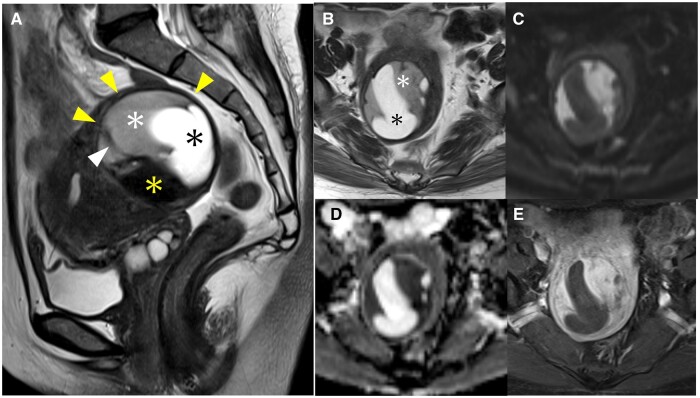

A low-grade endometrial stromal sarcoma (ESS) has a pattern of presenting as an intramyometrial mass and is often misdiagnosed as cellular leiomyoma or degenerative uterine leiomyoma. A low-grade ESS is a malignant tumour that requires total hysterectomy with bilateral salpingo-oophorectomy; while a leiomyoma is a benign tumour and could be acceptable for enucleation. As the treatment strategies differ between a low-grade ESS and leiomyoma, radiologists should be familiar with the characteristic MRI findings of a low-grade ESS. A 51-year-old woman with abnormal uterine bleeding had been observed for 2 years at a previous hospital for a uterine leiomyoma based on MRI findings. A contrast-enhanced MRI demonstrated an intramyometrial mass composed of three components with the hypointense rim on T2-weighted images (T2WI): the first component was a homogeneous solid structure with mild hyperintensity on T2WI with a low apparent diffusion coefficient value; the second component was cystic; the third component was a structure of low signal intensity on T2WI similar to the muscle. Although a degenerative uterine leiomyoma was a differential diagnosis, these MRI findings were suggestive of a low-grade ESS. A total abdominal hysterectomy, bilateral salpingo-oophorectomy, pelvic lymphadenectomy, and partial omentectomy were performed. The pathological diagnosis was a low-grade ESS. In a low-grade ESS, there are three major patterns of MRI findings: one of these patterns is the less popular but clinically important intramyometrial mass pattern, which can be misdiagnosed as a leiomyoma, and this case conformed to this pattern.